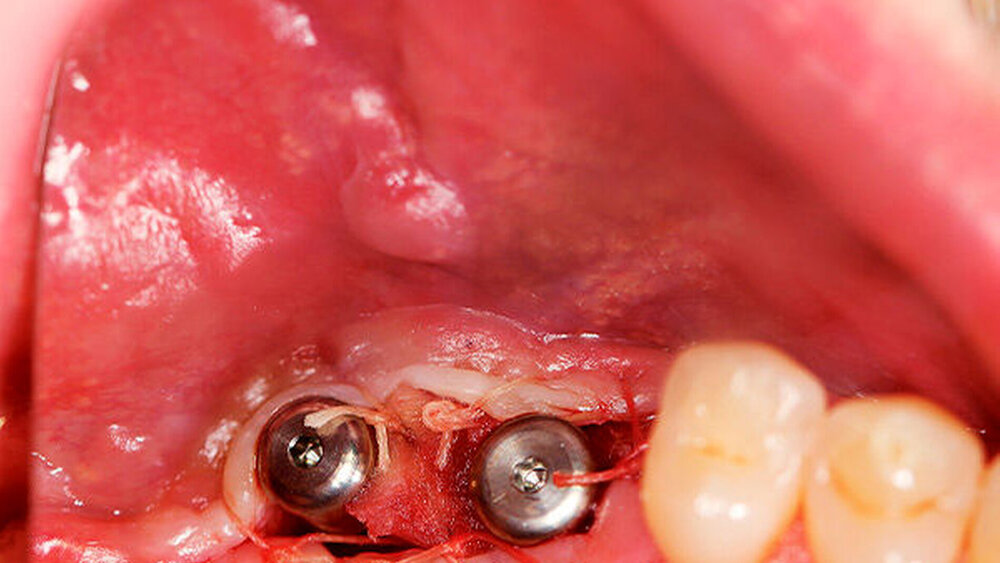

Ein 29-jähriger Patient stellte sich mit einer massiven Alveolarkammatrophie im rechten Unterkiefer in unserer Praxis vor. Diese lag in langen Jahren der Zahnlosigkeit begründet. Eine Beckenkammaugmentation kam für den Patienten nicht in Betracht. Dennoch wünschte er die Versorgung mit festsitzendem Zahnersatz. Nach ausführlicher Beratung entschied sich auch dieser Patient für eine Augmentation mit einem patientenindividualisierten allogenen CAD/CAM-gefertigten Knochenblock. Die DICOM-Daten des Unterkiefer-DVTs wurde an die Firma Zimmer gesendet, und es erfolgten wie im oben beschriebenen Fall eine virtuelle Planung und das virtuelle Design des allogenen Knochenblocks anhand der geplanten Implantatpositionen. Nach der üblichen Kontrolle und Freigabe des Chirurgen erfolgte die eigentliche Fertigung und Übersendung des Knochenblocks in die Praxis. Die Augmentation erfolgte auch in diesem Fall in Vollnarkose unter antibiotischer Abschirmung perioperativ mit Ampicillin. Die Schnittführung im Unterkiefer unterscheidet sich von der Sockelschnittführung im Oberkiefer aufgrund der Anatomie (N. mentalis). Auch bei diesem Patienten wurde eine tief im Vestibulum liegende bogenförmige Inzi‧sion durchgeführt, jedoch ohne die vertikalen Entlastungen. Nach streng subperiostaler Präparation erfolgte die Darstellung des N. mentalis. Die Vorbereitung des Spenderbetts sowie die Wässerung, Einpassung und Befestigung des allogenen Knochenblocks gestalteten sich wie im Fallbeispiel 1. Die Heilzeit des Knochenblocks dauerte ebenfalls sechs Monate. Zwei Implantate (Straumann) wurden nach krestaler Schnittführung in Lokalanästhesie eingebracht und heilten subgingival binnen drei Monaten ein. Aufgrund des massiven Volumenzuwachses war auch ebenfalls eine Vestibulumplastik im Zuge der Implantatfreilegung notwendig. Das Prozedere verlief ebenfalls wie im Fallbeispiel 1. Das freiliegende Gewebe wurde mit einer Kollagenmatrix abgedeckt. Dadurch konnte die Breite der befestigten Gingiva deutlich verbreitert werden.